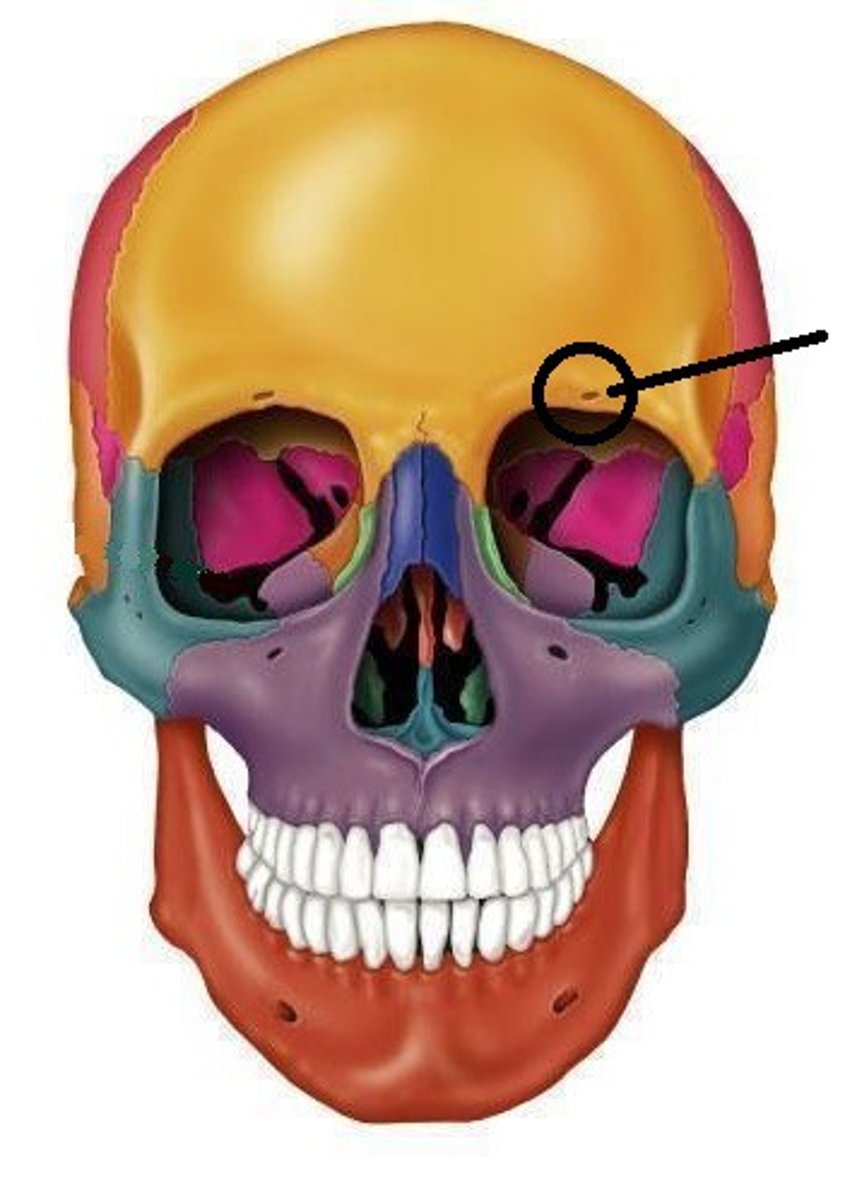

Parts of the Skull

39 Terms

37

New cards

infraorbital foramen

38

New cards

supraorbital foramen

39

New cards

external acoustic meatus